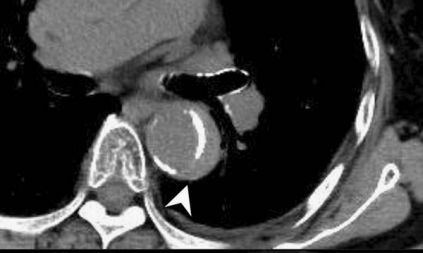

查到一篇文献,作者虽然用箭头标记了,并且是增强CT,但是鲁迅说:我大约肯定没有看出来,这是主动脉夹层!

图21